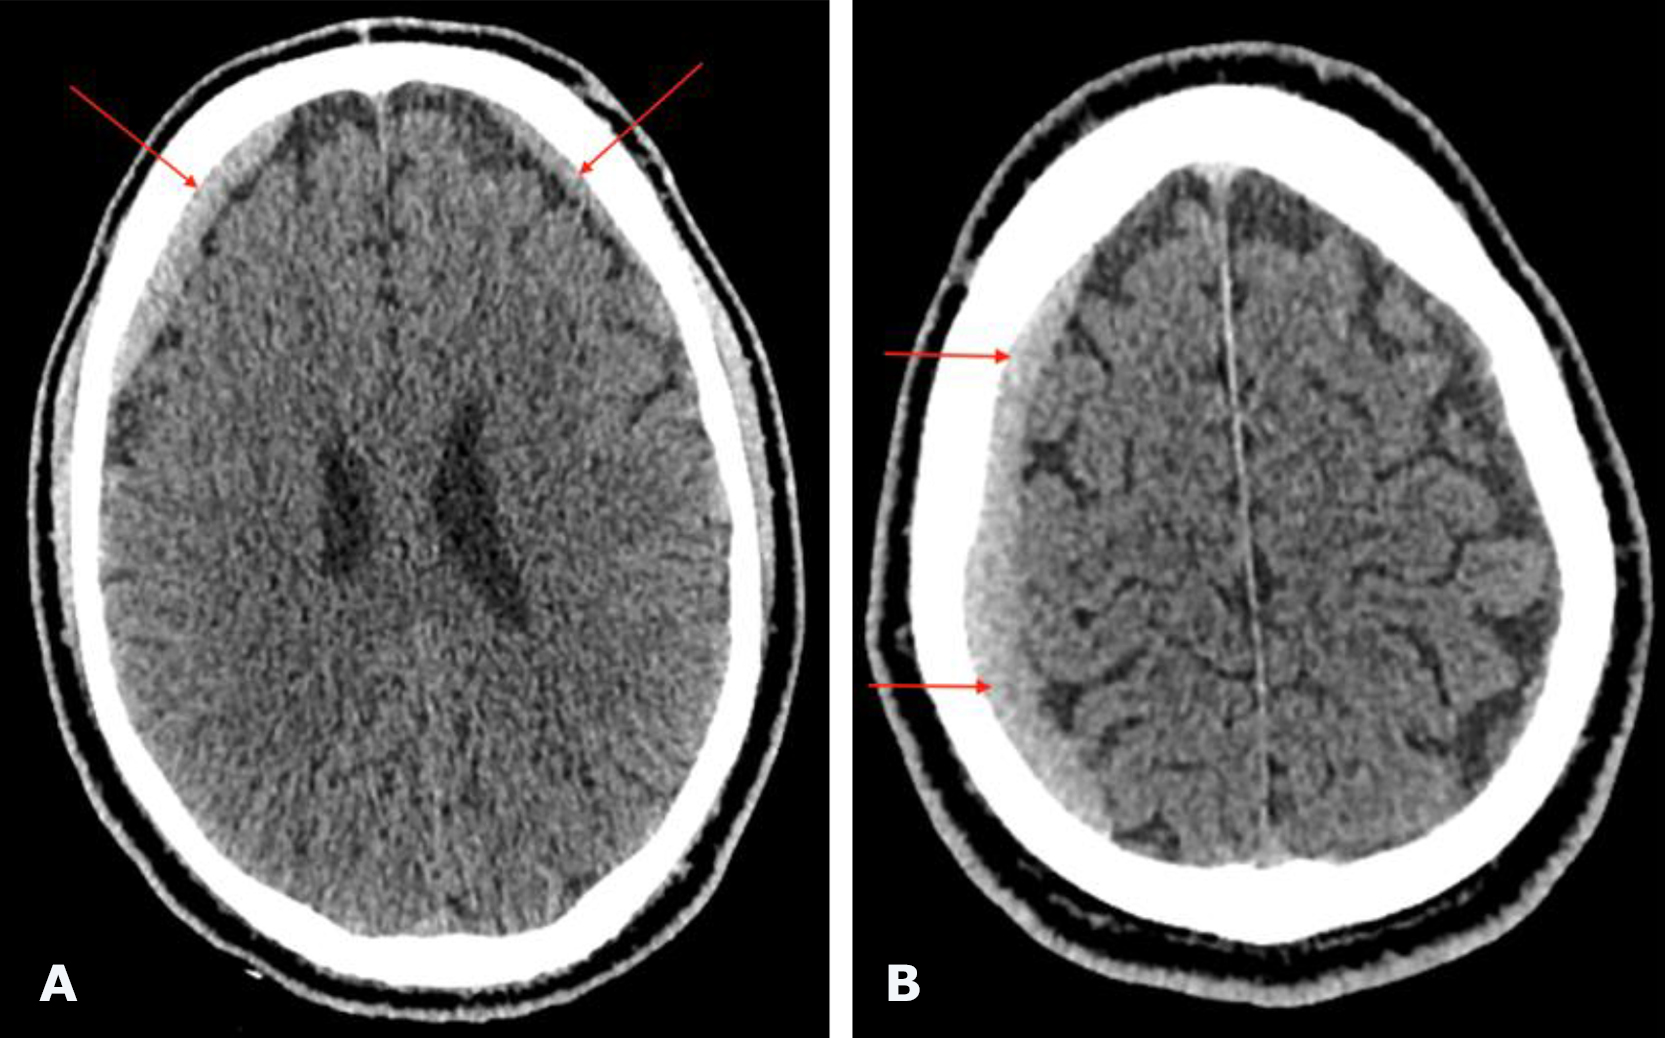

Non-contrast brain CT revealed bilateral chronic subdural hematomas (cSDH) in the frontal regions. The hematoma dimensions (thickness/length/height) were 8/48/48 mm on the left and 9/132/51 mm on the right. No displacement of the midline structures of the brain was detected (Fig. 1).

Fig. 1. Preoperative brain CT: A, B—axial projections demonstrating bilateral frontal cSDH (indicated by red arrows)

The postoperative course was uneventful. The neurological status remained unchanged, and no complications were observed. The patient was discharged from the hospital on postoperative day 2. Follow-up brain CT performed 1 month after surgery (Fig. 4) demonstrated complete resolution of bilateral frontal cSDH. At follow-up examination, regression of global cerebral symptoms was noted.

Fig. 4. Postoperative brain CT: A, B – axial projections. Purple arrows indicate the radiopaque embolic agent Onyx™ within the projections of the left and right MMAs